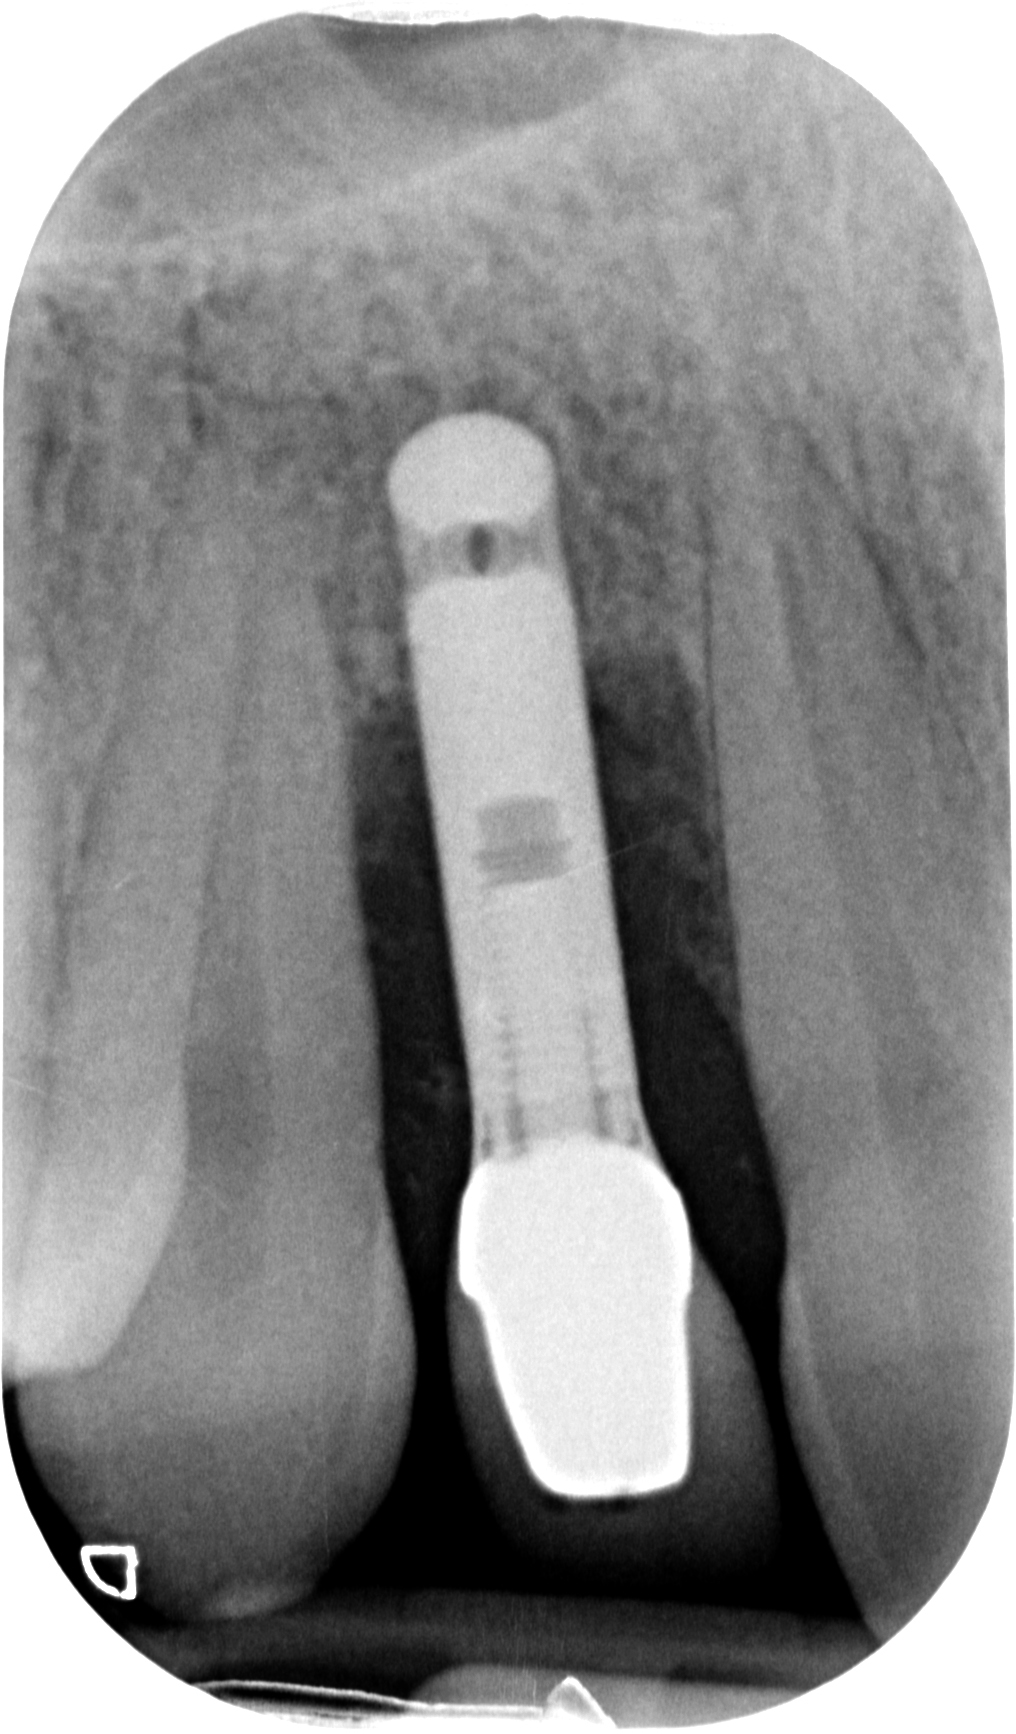

Ecco i risultati dei due casi:

Nel secondo, ad esempio, un ponte non è paragonabile alla soluzione ricostruttiva che ho attuato. Neanche lontanamente! Quindi è inutile dire

“il ponte sarebbe stato meno invasivo”

Perché il ponte non era la terapia giusta in questo caso! PUNTO! Avrebbe richiesto un sacrificio biologico drammatico in una ragazza di 28 anni e avrebbe portato ad un estetica diciamo “discutibile” vista la mancanza di volume rosa residuata dopo la rimozione dell’impianto infetto.